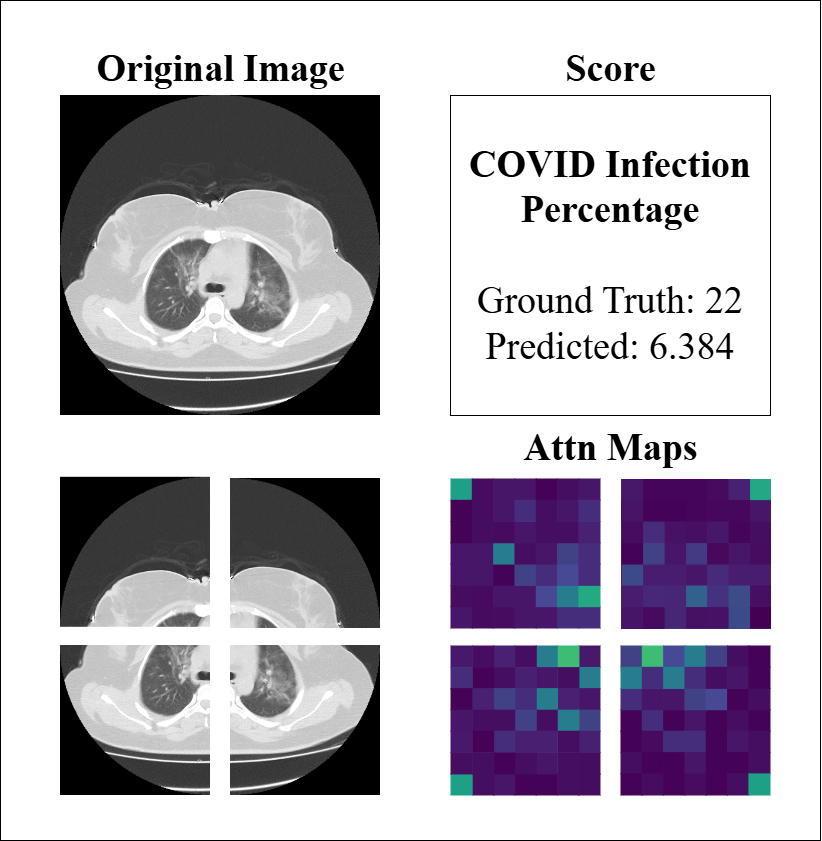

Similarly, to assess the model’s performance on CT imaging, we analyzed attention maps and prediction scores across representative cases, as illustrated in Figure 8. The examples demonstrate the model’s capacity to identify regions of COVID-19 involvement, with attention maps highlighting ground-glass opacities and consolidations that correlate well with infection percentage predictions in most cases (e.g., GT 60 vs. predicted 56.2). The spatial distribution of attention weights aligns with the predicted severity scores, reflecting the model’s ability to quantify disease burden through learned feature importance. However, the third example (GT 22 vs. predicted 6.4) reveals a substantial underestimation, despite attention maps showing patchy activations. This discrepancy may be attributed to CT-specific challenges such as partial volume effects, slice thickness variability, or subtle early-stage findings that complicate severity assessment. These observations emphasize that while the model effectively captures pronounced disease patterns, its performance may be limited by technical factors inherent to CT acquisition and early/mild disease manifestations.